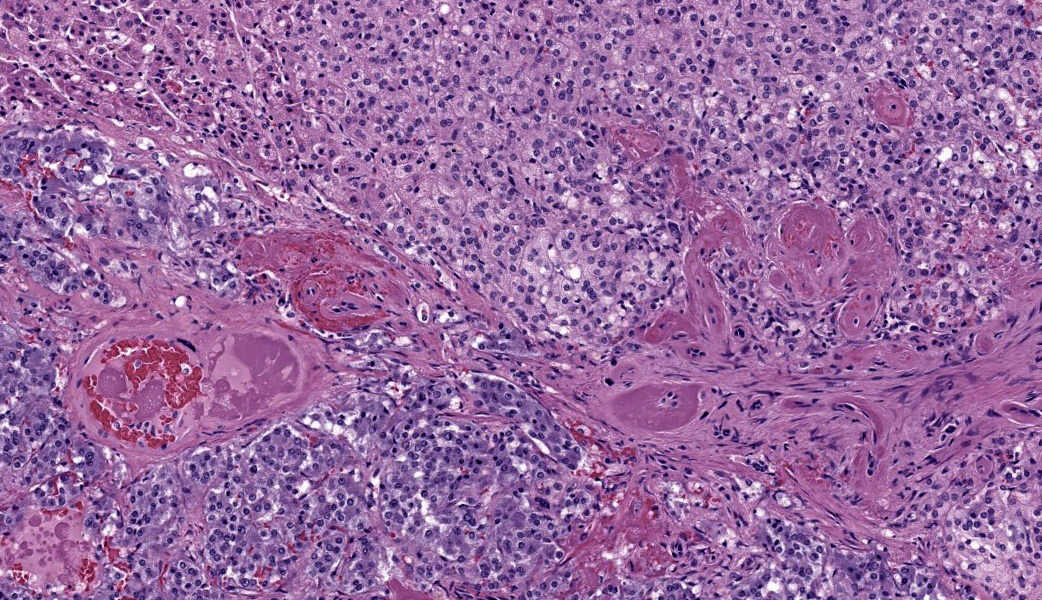

Adrenal glands: Multifocally, the small arteries and arterioles within the cortex and medulla show marked thickening of their walls, and narrowing or obliteration of their lumen, by intramural deposition of plasma proteins (consistent with hyaline arteriolosclerosis). Some vessels show intramural laminar deposits of plasma proteins (onion-skinning). Many sinusoidal vessels in the medulla are occluded by fibrin thrombi and are frequently effaced by hyaline material.Contributor's Morphologic Diagnoses:

Adrenal glands: Multifocal hyaline arteriolosclerosis.Condition: Hypertensive vasculopathy. Other diagnoses (tissues not included in the submission):

Adrenal gland, arterioles: Fibrinoid necrosis, chronic, diffuse, moderate, with fibrin thrombi and hemorrhage.JPC Comment:

Wrapping up conference discussion was a review of primary vs. secondary hypertension, which the contributor did an excellent job of covering in their comment. Hypertension causes hyaline arteriolosclerosis by causing endothelial damage, which then forces serum proteins from the blood out into the arteriolar walls where they accumulate and form deposits. This is traditionally referred to as ?fibrinoid necrosis?, and conference participants elected to use this term for the morphologic diagnosis. Additionally, the damage to the vessel walls from the increased pressure causes them to become tortuous and stimulates them to thicken and harden via smooth muscle proliferation and fibrosis as previously mentioned, reducing their elasticity and narrowing the lumen. This impairs blood flow and may result in thrombosis.3 In cases of hypertension, the most common presenting clinical sign in affected animals is acute blindness secondary to hypertensive retinopathy.